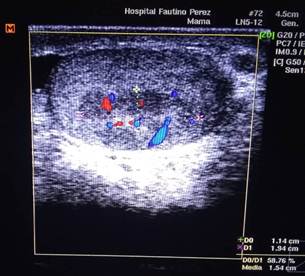

Ecografía Doppler escrotal (Figura 1): informó la presencia de una masa tumoral heterogénea, hipoecoica, localizada en la cara anterior y polo superior del testículo izquierdo, de 10 × 8 mm, con áreas internas quísticas y calcificaciones puntiformes. El estudio Doppler color mostró flujo sanguíneo interno aumentado (hipervascularización), patrón sugestivo de tumor de células germinales (Figura 2). En corte transversal se evidenció el carácter sólido de la lesión, con bordes irregulares y ausencia de sombra acústica posterior (Figura 3).

Figura 3: Corte transversal ecográfico. Se evidencia el carácter sólido de la lesión, con bordes irregulares y ausencia de sombra acústica posterior.